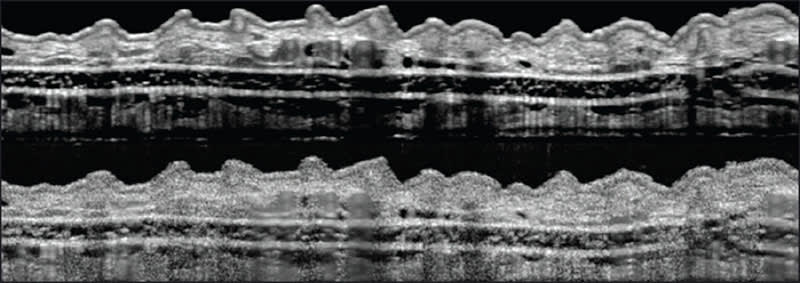

Now, averaging the successive images removed the speckles. The team was able to acquire detailed, essentially noise-free images of a living, anesthetized mouse's ear, its retina and cornea. They were also able to see sebaceous glands, hair follicles, blood vessels, and lymph vessels.

In a scan of a human finger, they saw an anatomical feature never before glimpsed with OCT: Meissner's corpuscle, a nerve bundle responsible for tactile sensations.